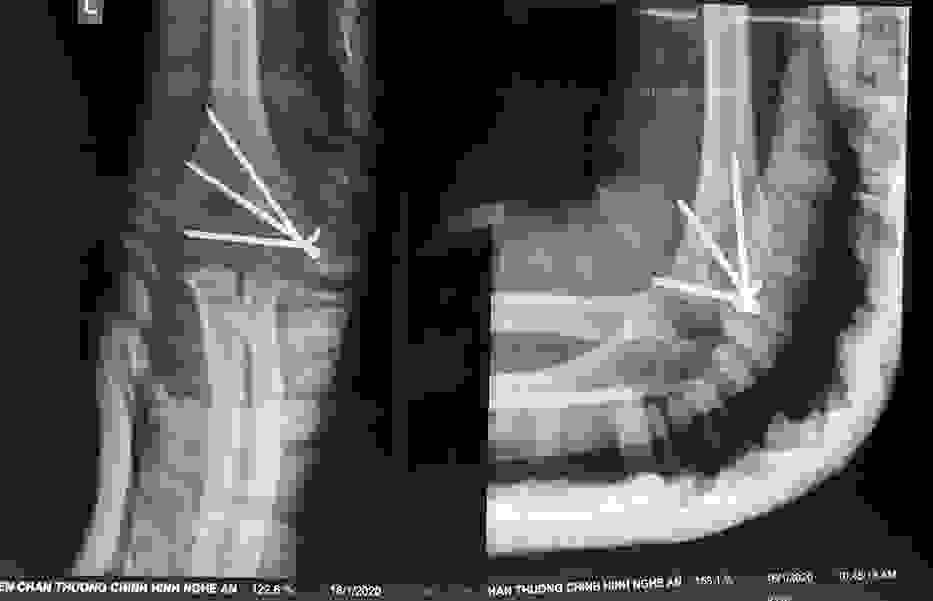

Phẫu thuật thành công ca bệnh hiếm gặp...khớp giả bẩm sinh xương chày

26/06/2019 17:00

Đã xem: 3461

Bệnh viện Chấn thương- Chỉnh hình Nghệ An, vừa phẫu thuật thành công cho bệnh nhi khớp giả bẩm sinh xương chày